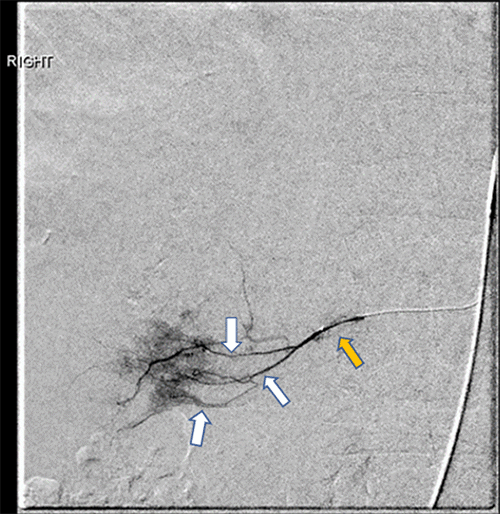

In anticipation of significant intraoperative bleeding during resection of the massive hemangioma, the patient underwent preoperative angioembolization the day prior to surgery. Hepatic angiography identified the hemangioma’s arterial supply: the right inferior phrenic artery (Figure 2) and three secondary branches of the right hepatic artery (Figure 3). All four vessels were successfully embolized with Gelfoam slurry. The procedure was well-tolerated, and no complications were reported either during the procedure or in the post-embolization period. The patient then proceeded to surgical resection of the hemangioma the following day.

Figure 3. Pre-embolization Angiogram Demonstrates Tumor Arterial Supply. Published with Permission

The right hepatic artery (yellow arrow) supplies the tumor (not shown) via three second-order branches (white arrows). Opacification of these branches confirms their contribution to tumor blood flow.